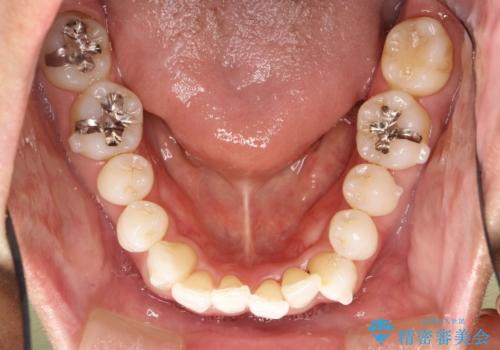

右上の前から2番目の歯が引っ込んで、下の前歯にはガタガタがありました。

上下の歯と歯の間を少量ずつ削りスペースを作り、インビザラインにて並べる計画としました。